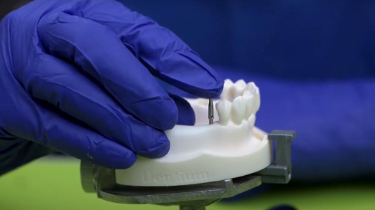

Dentium SuperLine Implant Placement on a Dummy Model

Recently, we treated a 21-year-old female patient who came to our clinic with a grossly decayed lower left first molar (#36). Due to the severity of the decay, extraction was necessary, and to prevent bone loss and restore her function we opted for an implant placement using a Dentium SuperLine implant.

Immediate implant placement offers several benefits, including preserving bone and minimizing treatment time. To ensure long-term success and stability, we selected Dentium SuperLine implants, known for their high quality and excellent osseointegration.